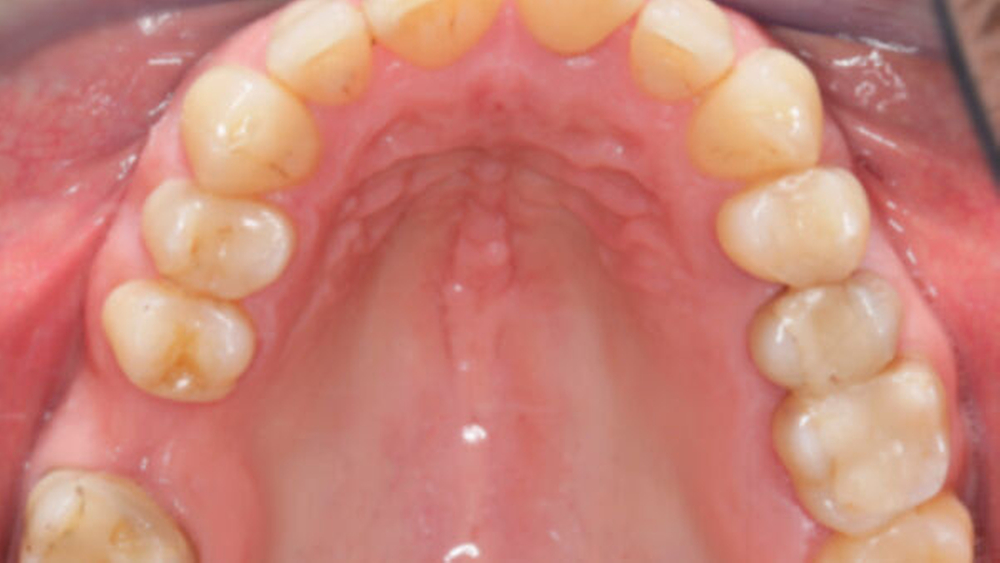

Das Fallbeispiel beschreibt das Vorgehen bei einem 38-jährigen, gesunden Patienten mit einer Einzelzahnlücke in Regio 16 (Abbildung 1). Laut Anamnese lagen keine Kontraindikationen für eine Implantation vor. Es bestand eine suffiziente Mundhygiene. Alle notwendigen Vorbehandlungen waren abgeschlossen. Das Implantat konnte wie geplant inseriert und nach Abschluss einer dreimonatigen Einheilzeit mit einer transokklusal verschraubten monolithischen Keramikkrone aus Lithiumdisilikat versorgt werden. Seit der Implantation im Mai 2019 wurden keine Komplikationen dokumentiert.